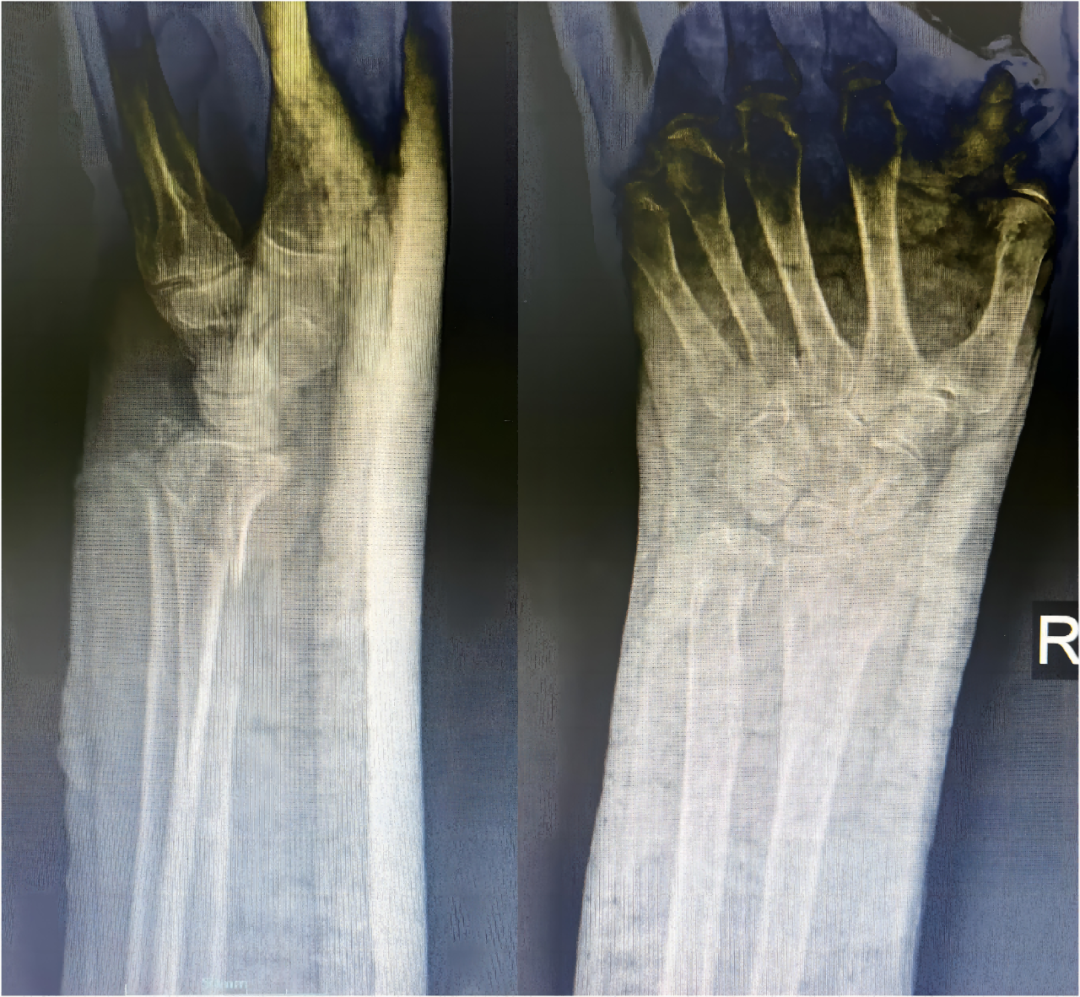

近日,我科收住一位高齡患者,孫某某,女,82歲,患者2小時(shí)前因摔傷致全身多處腫痛、伴活動(dòng)受限。入院后診斷:1.右股骨粗隆間粉碎性骨折;2.右尺橈骨遠(yuǎn)端粉碎性骨折;3.右鎖骨骨骨折;4.右肱骨大結(jié)節(jié)骨折;5.右恥骨下肢骨折;6.重度骨質(zhì)疏松。 鑒于患者屬高齡,損傷重,病情復(fù)雜,入科后科主任魏國(guó)華帶領(lǐng)關(guān)節(jié)骨科醫(yī)護(hù)團(tuán)隊(duì)積極完善相關(guān)檢查、科學(xué)制定治療方案,充分發(fā)揮中醫(yī)骨傷的治療優(yōu)勢(shì),保守與手術(shù)相結(jié)合,對(duì)右尺橈骨遠(yuǎn)端粉碎性骨折行手法復(fù)位石膏托外固定術(shù)。 排除手術(shù)禁忌后,在腰硬聯(lián)合麻醉下行右股骨粗隆間粉碎性骨折閉合復(fù)位PFNA內(nèi)固定術(shù),其余疾病行保守治療,術(shù)后經(jīng)活血化瘀、益氣養(yǎng)血等積極對(duì)癥治療,患者肢體功能恢復(fù)良好,已康復(fù)出院。 股骨粗隆間骨折是老年人常見(jiàn)損傷,俗稱人生最后一次骨折。老年人骨質(zhì)疏松,肢體不靈活,當(dāng)下肢突然扭轉(zhuǎn)、跌倒或使大粗隆直接觸地?fù)p傷,甚易造成骨折。由于粗隆部受到內(nèi)翻及向前成角的復(fù)合應(yīng)力,引起髖內(nèi)翻畸形和以小粗隆支點(diǎn)的嵌壓形成小粗隆蝶形骨折。亦可由髂腰肌突然收縮造成小粗隆撕脫骨折。粗隆部骨質(zhì)疏松脆,故骨折常為粉碎型。 就診地址:酒泉市中醫(yī)醫(yī)院關(guān)節(jié)骨科?? ?? 門診部:二樓205診室 住院部:綜合樓6樓住院部